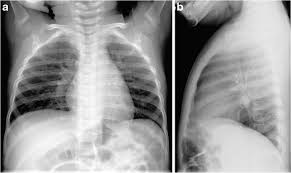

A pneumonia eosinoffii~a aguda (pea) e uma doe~ rara, de etiologia desconhecida, caracterizada por eosinofilia pulmonar marcada, geralmente niio associada a aumento dos eosinofilos no sangue. Pneumonia este o infectie pulmonara obisnuita in care saculetii pneumatici ai plamanilor devin inflamati. The most common one is streptococcus (pneumococcus), but other bacteria can cause it too. Pneumonia can be generally defined as an infection of the lung parenchyma, in which consolidation of the sections bacterial pneumonia. Streptococcus pneumoniae (j13) is the most common bacterial cause of pneumonia in all age groups except. Pneumonia este o inflamație a țesutului pulmonar, de obicei cauzată de o infecție virală sau bacteriană. Clinical presentation bacterial pneumonia has symptoms similar to other pneumonia. When pneumonia is caused by streptococcus pneumoniae, mycoplasma pneumoniae, or other bacteria, it's called bacterial pneumonia. Bacterial pneumonia is a type of pneumonia caused by bacterial infection. New conceptual models of pulmonary microbiology and pneumonia pathogenesis. Pneumonia por pneumocystis jirovecii 4. Aceste saculete se pot umple, de asemenea, cu lichid, puroi si resturi. Bacterial pneumonia is characterized by exudative solidification (consolidation) of the pulmonary tissue, which is caused by bacterial invasion of the lung parenchyma.

Pneumonia este o inflamație a țesutului pulmonar, de obicei cauzată de o infecție virală sau bacteriană pneumonia bacteriana. This illness can affect both children and adults.